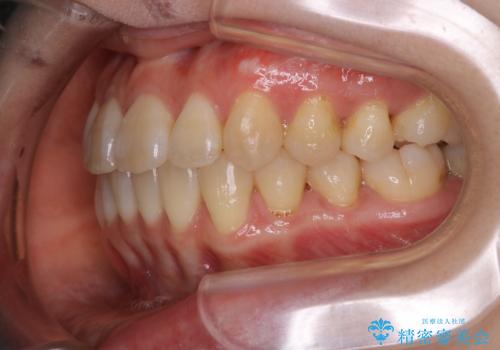

- 前歯のがたつきが気になるとご相談にいらした方です。右側前歯部のクロスバイトの他、左側にもシザーズバイトが認められたため、インビザラインにて治療を行いました。出産直後のため、ご自身の時間がなかなか取れないとの事で、最小限の来院回数で治療を勧められるように計画しました。

患者様ご自身で使用時間をしっかり管理して頂くことを条件に、最低限の来院回数で治療を進めていきました。20時間以上の使用を厳守して頂けたことで、少ない来院回数にて治療を終了することが出来ました。前よりも噛みやすくなったと大変喜んでいただけました。